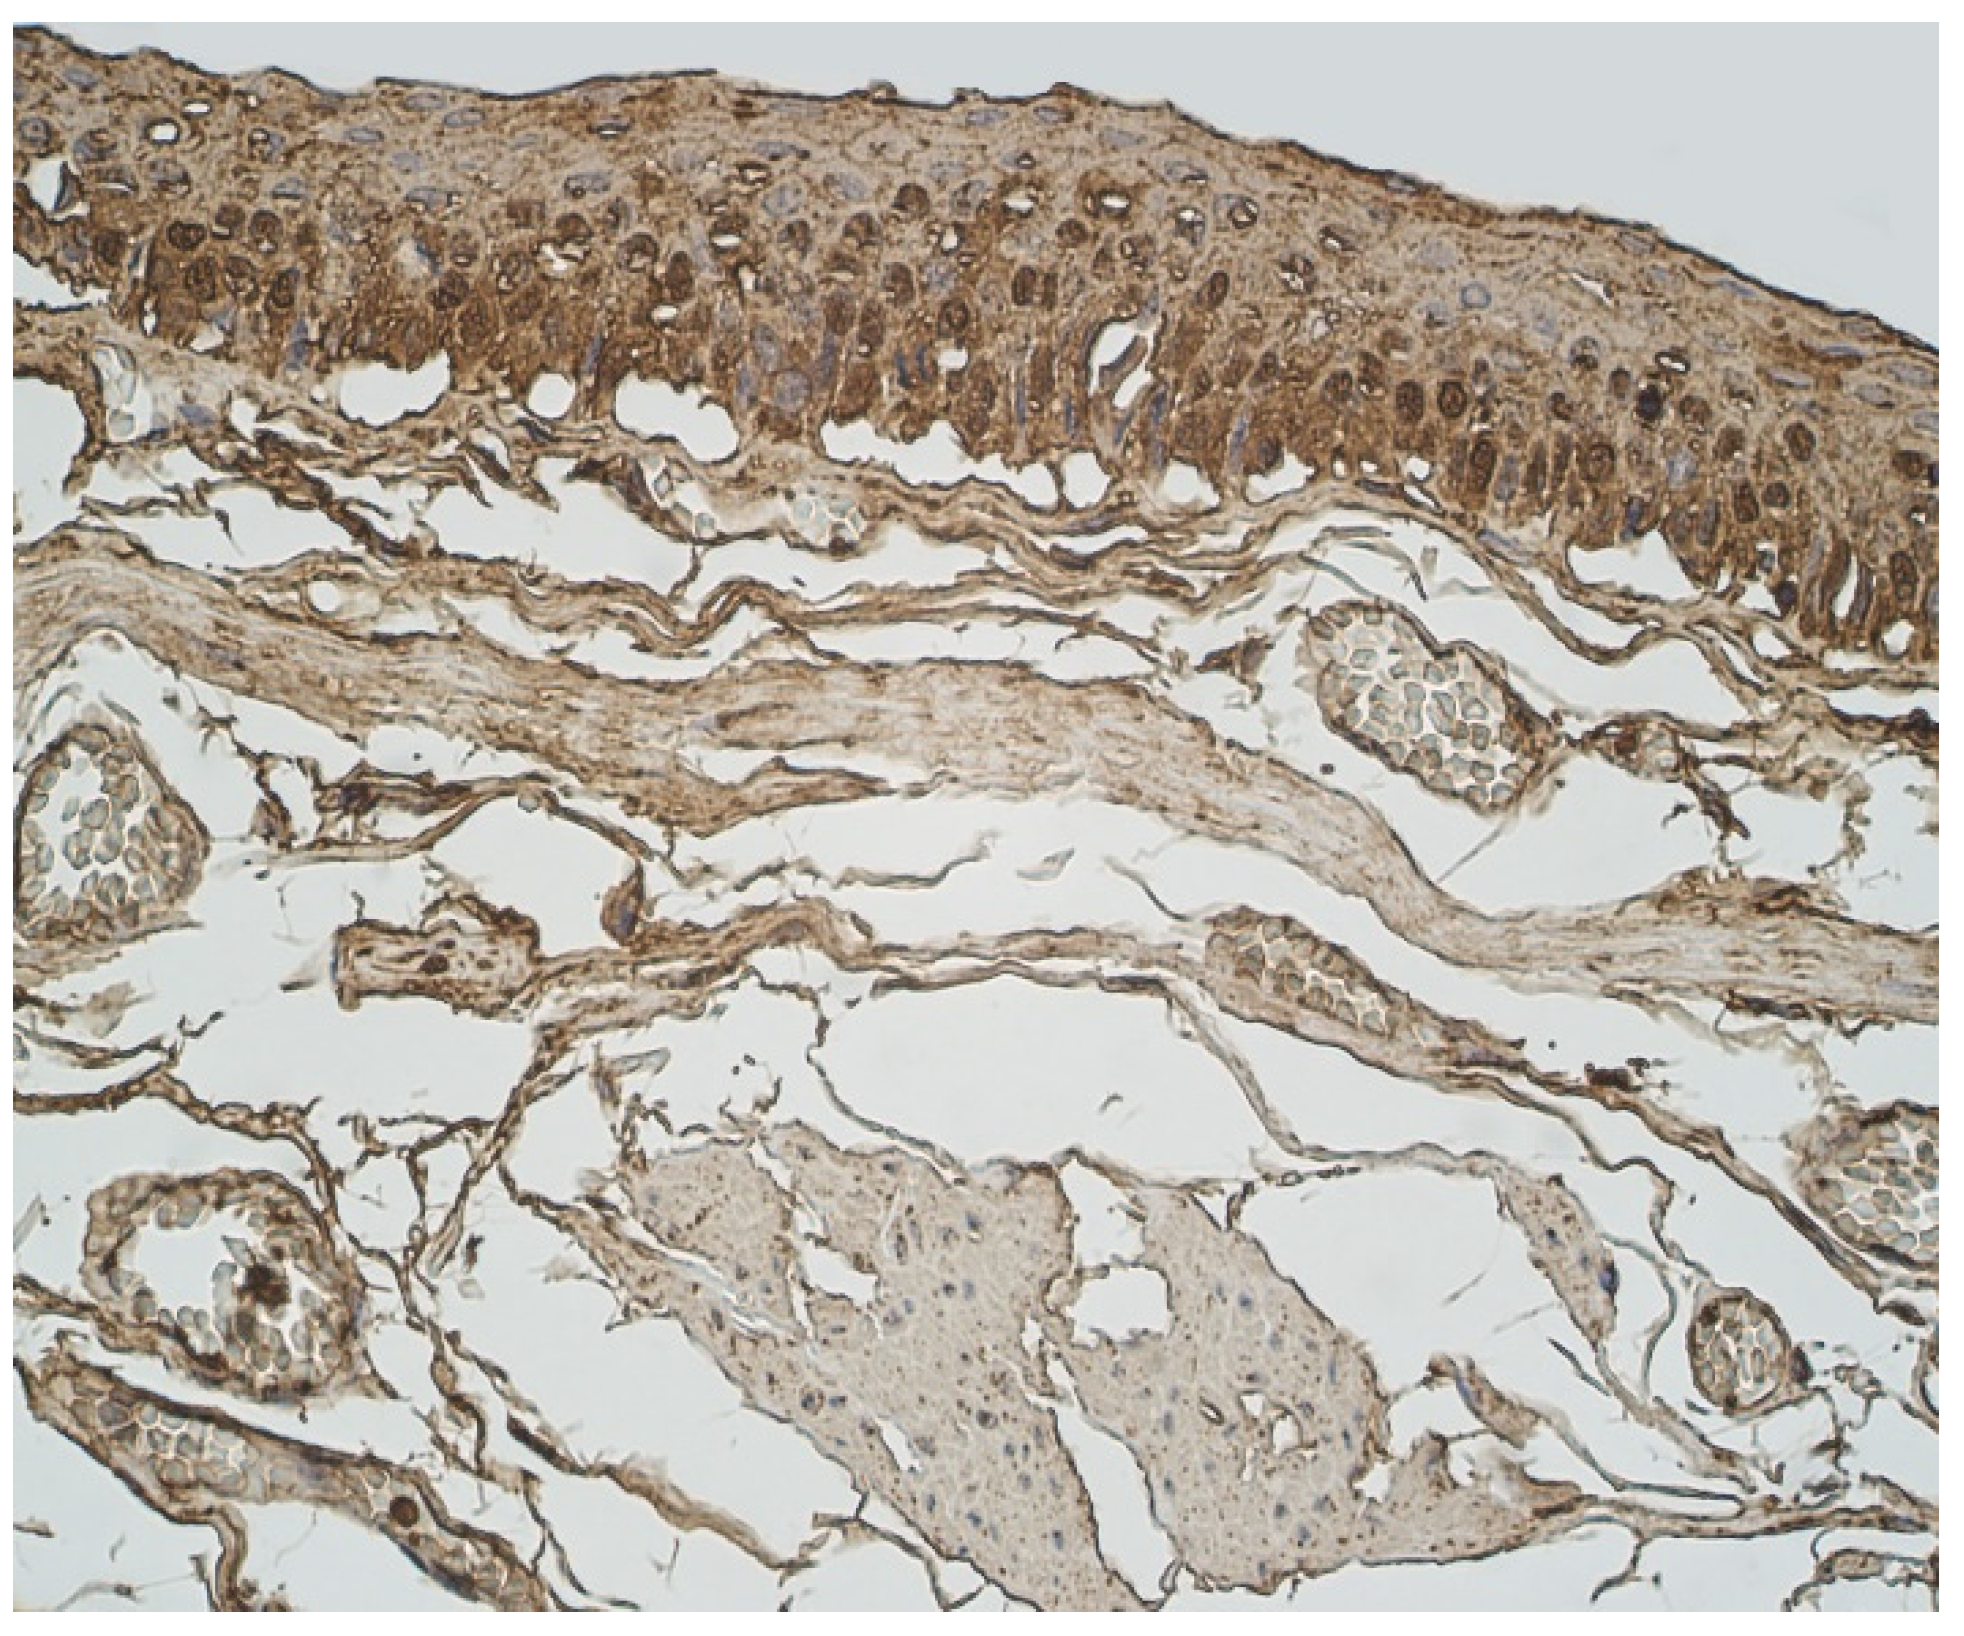

3.1. Tissue Review

3.2. Immunohistochemical (IMH) Data